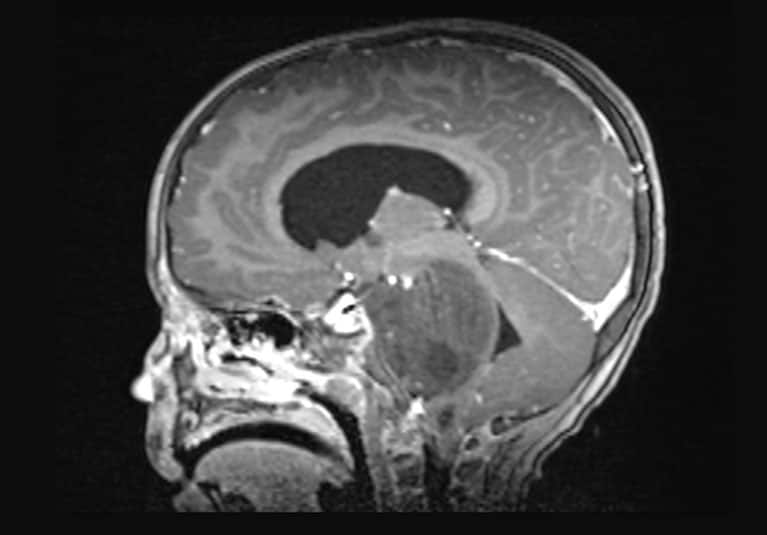

Unique imaging protocol facilitates moyamoya disease management

Mayo Clinic's protocol can provide a comprehensive evaluation of the underlying severity of hemodynamic effects in individuals with this challenging condition.